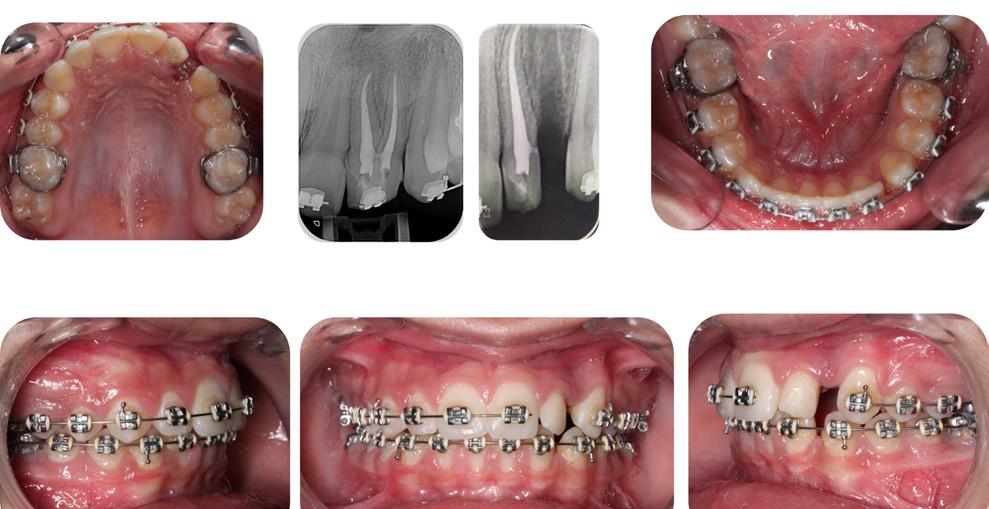

Finally, after 21 months of treatment, the patient and the parents consented to the odontectomy of the maxillary first bicuspids. The informed consent forms for the extractions and placement of TADs were signed by the parent, and all questions were answered. Risks, benefits, alternatives, and the result of no treatment at all were reviewed. Immediately after the odontectomy of #14(5) and #24(12), 1.6 x 8.0 mm AnchorPro (OrthoOrganizers) TADs were placed just mesially to the maxillary second bicuspids.6 In office power arms (a .018 x.025 SS) were fabricated and bonded to the buccal surface of the maxillary cuspids, just above the bracket.7 The purpose of the power arm is to place the applied force as close to the center of resistance of the tooth as possible. In this manner the line of action (power hook to the TAD) is parallel to the occlusal plane. The source of the force is an EC, and it must be replaced at least bi-weekly. Both arches had a .018 SS arch wire. There was a small off-center bend (tip-back, gable bend) “V” pointing occlusally, mesial to the maxillary second bicuspids.8 The purpose of this bend is to keep the roots parallel during the translation of the cuspids. There was a small OCS between #21(9) and #23(11) to shift the maxillary midline to the right. Another OCS was placed between #32(23) and #34(21) to facilitate the alignment of the mandibular left cuspid (Figure 8-A, B, C, D).

To prevent a disto-lingual moment (rotation) of the maxillary cuspids we attached PC from the lingual button on the cuspids to the framework on the hyrax. The anterior portion of the Hyrax was cut off and the remaining portion served as a TP arch for posterior anchorage. At this point, we were 25 months into treatment (Figure 9-A, B, C, D). The hyrax was removed after 30 months of treatment.

Figure 8A: TADs in situ, frontal view 8B: TAD in situ, right lateral view 8C: TAD in situ, left lateral view 8D: Power arms Figure 9A: Maxilla, occlusal view 9B: Maxilla, occlusal view 9C: Maxilla, occlusal view Figure 9D: After the removal of the Hyrax, occlusal view Figure 10A: Center bend “V” pointing gingivally Figure 10B: OCS between the cuspids and the central incisors Figure 10C: Composite build-ups on the mandibular first molars Figure 10D: Adrian “U” bend spring

Please view the post-treatment images at the time of insertion of the retainers (Figure 14 - A, B, C. D, E, F, G, H, I, J, K, L, M, N).9

Figure 14H: Post-treatment, mandible, occlusal view

Figure 14A: Post-treatment, panoramic radiogram

Figure 14B: Post-treatment, cephalometric radiogram

Figure 14C: Post-treatment periapical radiograms

Figure 14G: Post-treatment, occlusal view

The final panoramic radiogram reveals impacted wisdom teeth and distally tipped mandibular second molars that partially erupted. The final periapical radiograms of the maxillary anterior teeth reveal minimal root resorption and acceptable angulation except for #12(7), where the root remained distally oriented.